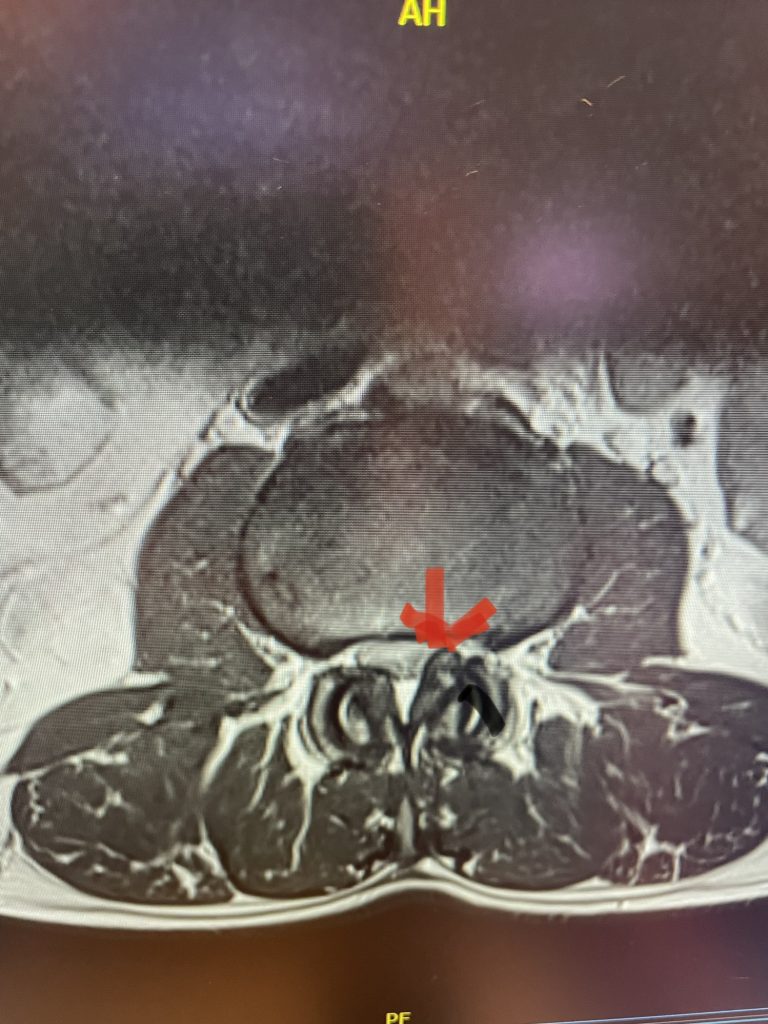

Figure 1: Axial lumbar spine images demonstrating the descent of the nerve root below the subarticular recess as it rounds the pedicle and enters the neural foramen. On the left shows the normal anatomy and on the right showing the descending nerve root being compressed in the lateral recess by a hypertrophied superior process with medial protrusion.

Figure 2: Cartoon axial image of the lumbar spine showing (arrow) severe narrowing of the lateral recess with flattening of the nerve root compared to a normal nerve root on the opposite side.

Figure 5: Axial T2-weighted MRI demonstrating severe bilateral lateral recess stenosis secondary to thickened ligamentum flavum. Notice the prominence of the left ligamentum in the subarticular recess.